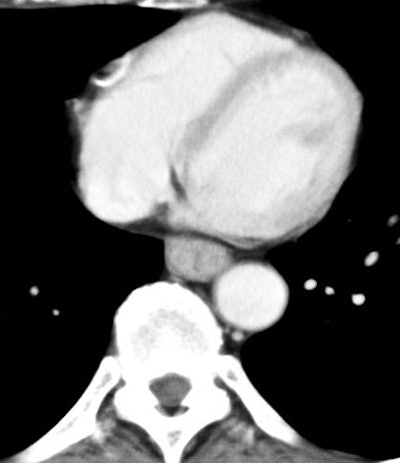

![]() |

| Arterial-phase image of 60-year-old male with T1b esophageal cancer. The tumor is clearly enhanced on the arterial phase (arrow). The lesion was T1b at surgery. All images courtesy of Dr. Shigeaki Umeoka. |